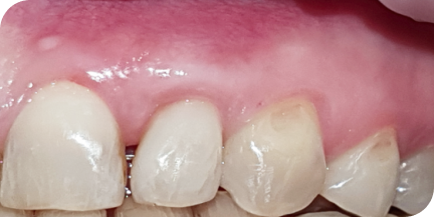

Пациентку (Екатерина, 55 лет) в нашу клинику отправили из другой клиники наши коллеги. Цель — вылечить и нарастить десну перед протезированием зубов.

Это был непростой клинический случай с наращиванием десны

в эстетически значимой зоне.

На фотографиях исходное состояние, состояние спустя год после наращивания и 5 лет после наращивания. Результат стабилен.

Десна после наращивания никогда не опустится, если пациент соблюдает все рекомендации врача: приходить на регулярные профилактические осмотры.